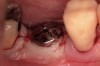

Approximately 18 weeks following extraction and grafting, full-thickness flaps were reflected, revealing complete osseous regeneration of the original defect (Figure 8). The osteotomy was initiated with the same trephine bur to harvest a core of representative bone present at the site of implant insertion. Implant placement proceeded without alteration from the manufacturer's protocol by inserting a 4.8-mm x 8-mm fixture with primary, tactile, stability, and transmucosal healing properties. At about 8 months postplacement, the implant was restored with a custom abutment and cement-retained crown (Figure 9).

Figure 8  Re-entry showing complete bone regeneration.

Figure 8